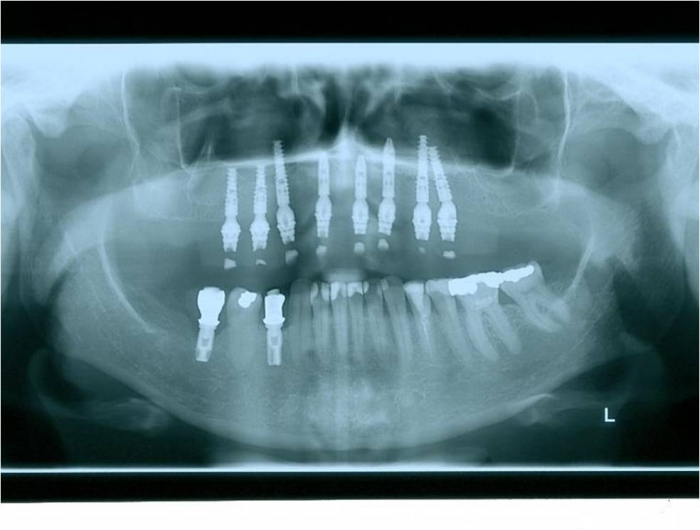

Raio x inicial